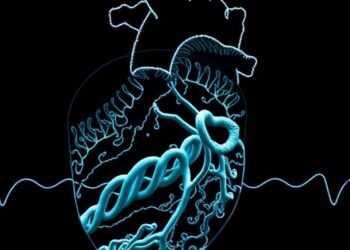

Barua Develops High-Resolution Harmonic Fingerprinting Technique from Sparse Sampling to Disaggregate Complex Cardiovascular Diseases

Barua Advances Predictive Maintenance and Diagnostics of Complex Naval Systems Through High-Resolution Harmonic Fingerprinting In a transformative leap for naval...